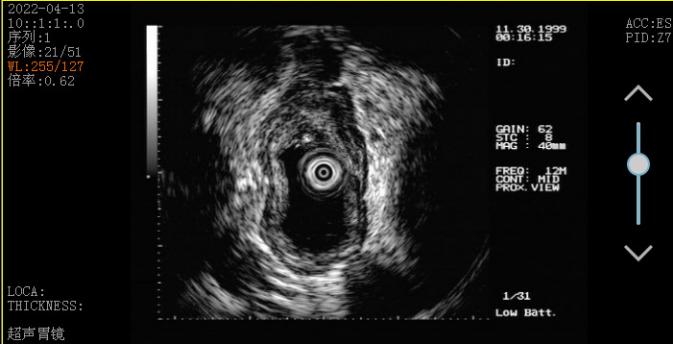

那王叔到底得了什么病差点被认为是癌症?难道这只是普通的溃疡吗?此时张涛提议,“王叔,咱们再做个超声胃镜吧”。超声胃镜可以看到普通胃镜看不到的层面,很快王叔接受了进一步超声胃镜检查,并再次活检。超声胃镜提示1.食管溃疡性质待查(结核?Ca?待病理);2.反流性食管炎(A级);3.慢性非萎缩性胃炎伴糜烂 。

病理结果再次提示炎症改变,可见肉芽肿形成。这下大家都庆幸王叔至少算是捡回一条命了,但是到底是什么病还是不清楚,下一步又该怎么走呢?王叔说:“张主任,我就靠你啦!”面对患者的信任,科室针对这个病例组织了科内大会诊。